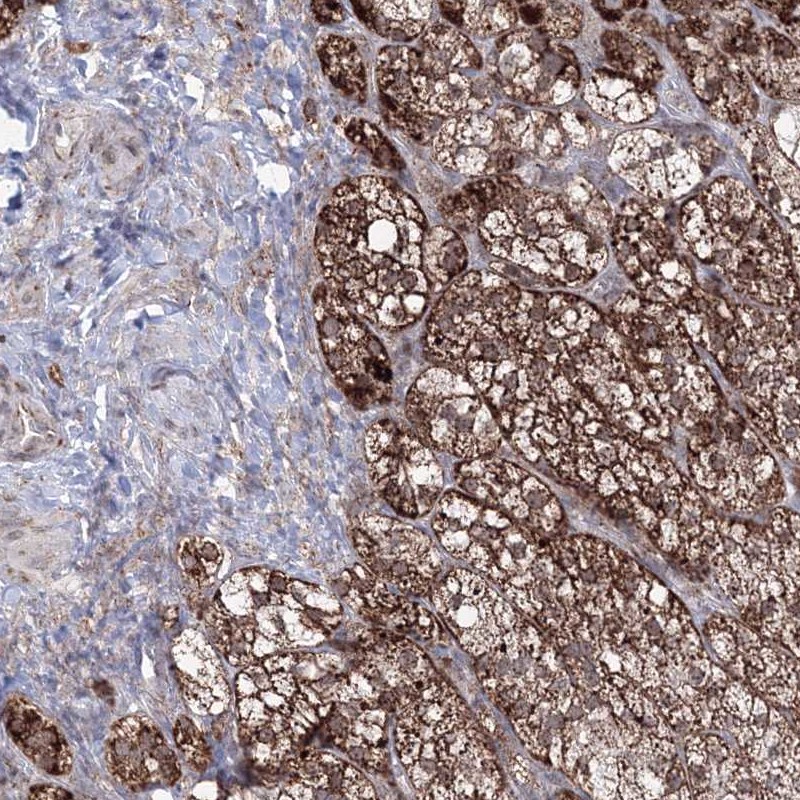

Immunohistochemistry analysis in human adrenal gland and pancreas tissues using HPA036984 antibody. Corresponding GRSF1 RNA-seq data are presented for the same tissues.